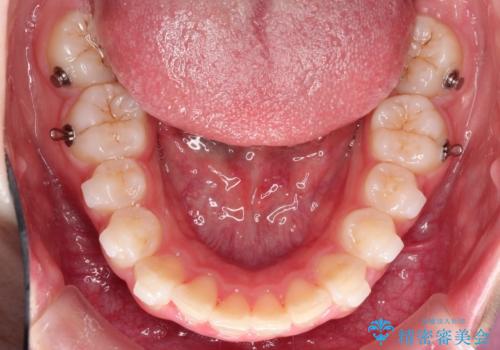

- 矯正装置

- インビザライン

- 前歯の隙間と、出っ歯に見えることを主訴に来院されました。

できるだけ目立たない装置をご希望されましたので、インビザラインにて治療を行いました。

治療中は、できるだけ前歯を下げることができるように”顎間ゴム”を使用します。

”顎間ゴム”を利用することで、奥歯を後ろに動かす力を強めることができます。